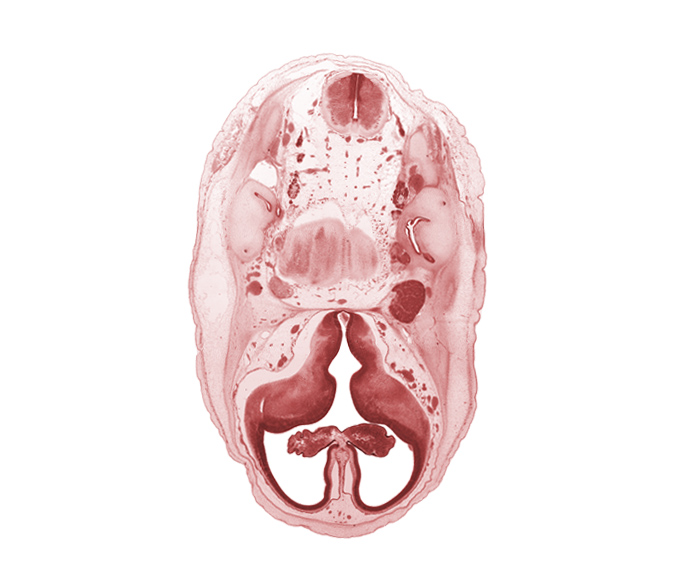

Carnegie Embryo #462 | Location: 5-04-03

Keywords: accessory nerve (CN XI), artifact separation(s), choroid plexus, facial nerve (CN VII), glossopharyngeal nerve (CN IX), hypothalamic sulcus, internal carotid artery, interventricular foramen, lateral ventricle, lateral ventricular eminence (telencephalon), medial ventricular eminence (diencephalon), myelencephalon (medulla oblongata), pons region (metencephalon), superior ganglion of vagus nerve (CN X), vestibulocochlear nerve (CN VIII)

Source: The Virtual Human Embryo.